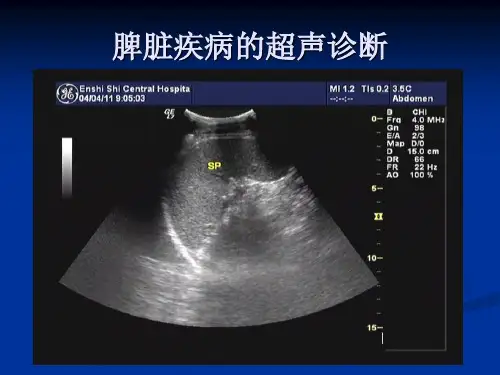

脾脏超声检查是临床诊断脾脏疾病的重要手段之一。

脾脏超声检查技术首选高分辨力灰阶实时超声诊断仪。

探头以凸阵或线阵探头为好。

探头频率多用3.5~5.0MHz,儿童可用5MHz。

检查体位1.常规采用右侧卧位或右侧450卧位。

检查方法标准断面检查方法冠状断面扫查仰卧位,将探头置于左侧腋中线与腋后线之间,使声速朝向脊柱,以显示脾肾图形及其与脊柱关系。

并测量最大长经。

前倾冠状断面扫查由上诉冠状断面,将探头声速平面向前腹壁慢转动,直至显示脾门和脾门血管断面时冻结。

测量脾传统长经和后经。

同时动态观察脾脏与邻近器官如肾、胃和膈的关系,并注意有无胸腔积液、腹水和膈下积液。